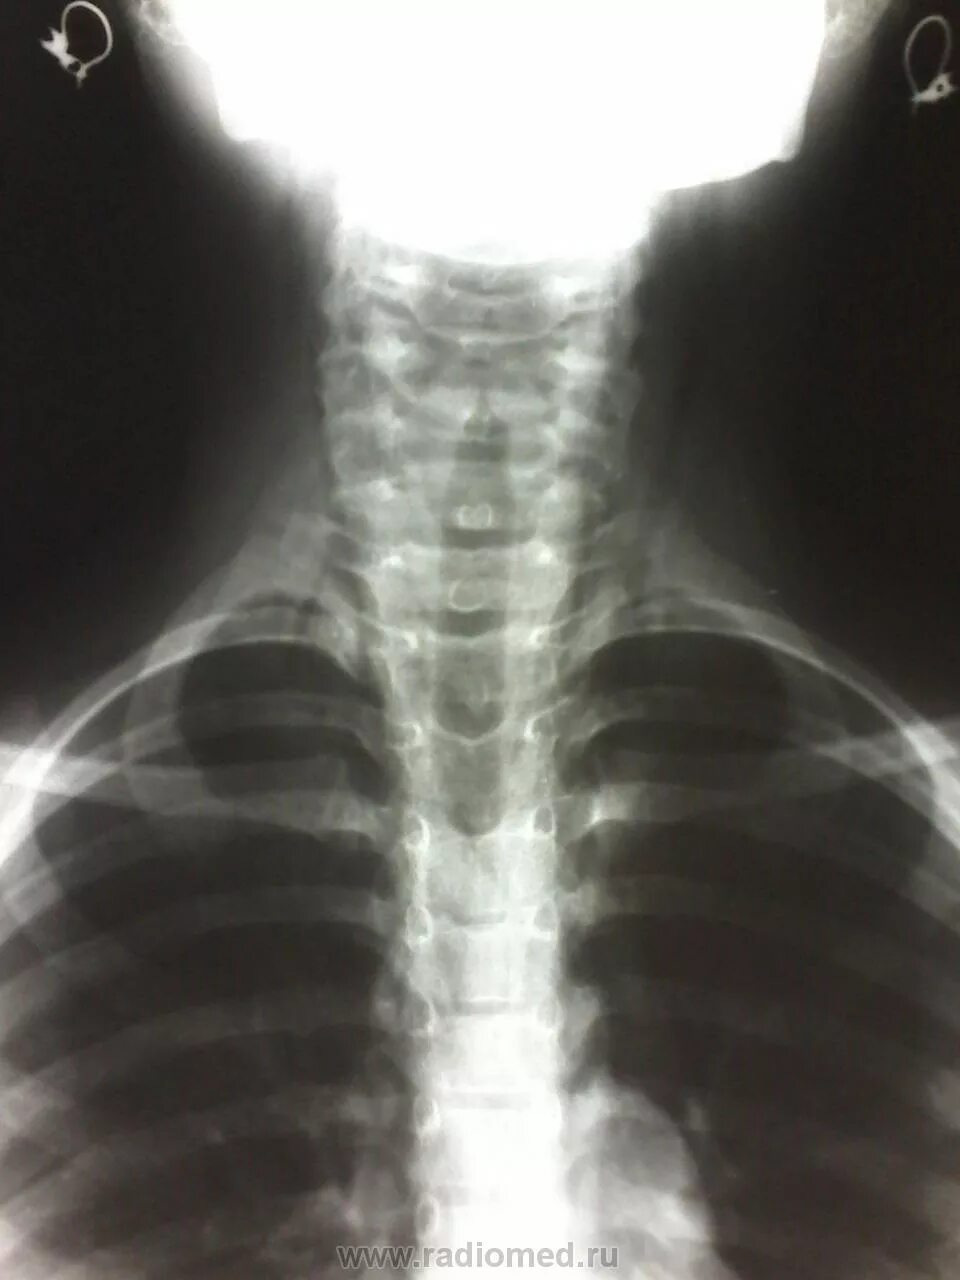

Эмфизема мягких